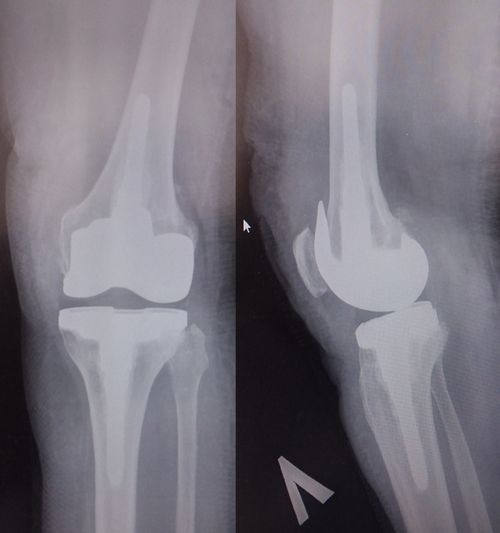

КРАСНОЯРСКИЙ КРАЙ, /НИА-КРАСНОЯРСК/. Такие операции технически сложные, их проводят пациентам, у которых после перелома сформировалась грубая анатомическая аномалия, имеются посттравматические, поствоспалительные изменения суставов, а также при «нестандартных» деформациях костей.

Ранее пациенты с тяжелой ортопедической патологией для проведения больших реконструктивных операций направлялись в специализированные федеральные клиники. Сегодня данный вид высокотехнологичной медицинской помощи доступен по полису ОМС на территории Красноярского края. Врачами БСМП в этом году были успешно прооперированы несколько пациентов со сложной ортопедической патологией с достигнутыми положительными результатами, отмечает пресс-служба регионального минздрава.

Для проведения первично-сложного эндопротезирования в больнице имеется необходимое оборудование, расходные материалы, а также подготовленные специалисты.